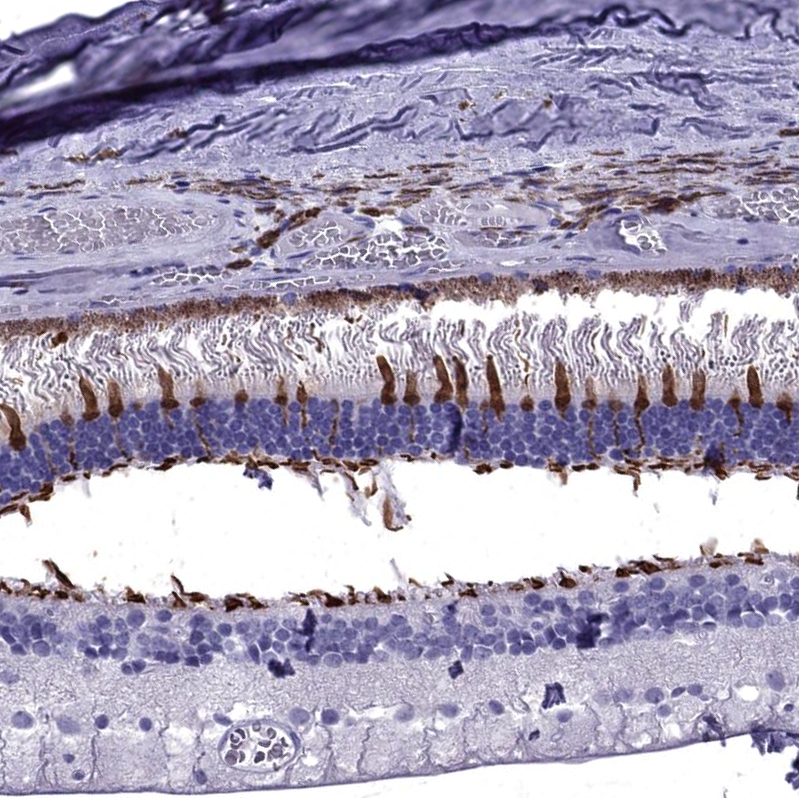

Immunohistochemical staining of human eye, retina shows strong cytoplasmic positivity in cones.